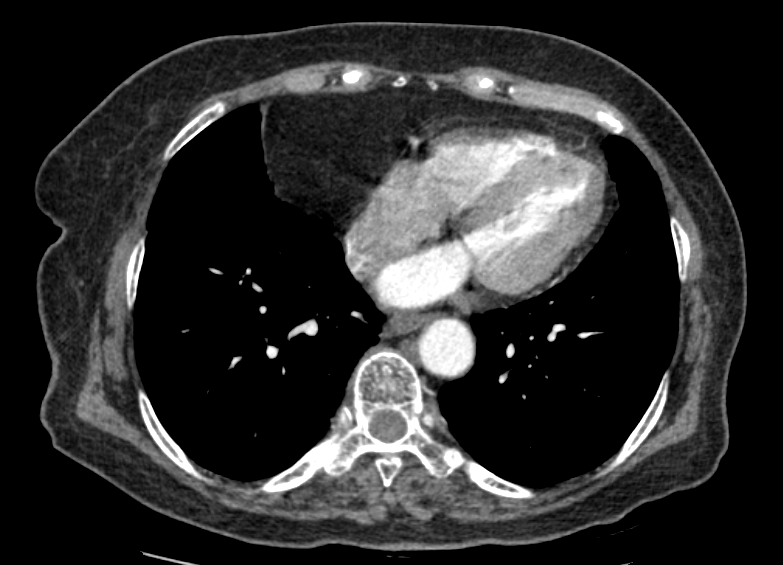

F/73

DM, HTN °ú°Å·Â ÀÖ´Â ºÐÀ¸·Î hip osteoarthritis ·Î THR ½ÃÇà ¿¹Á¤ÇÏ´ø Áß preop CXR abnormality ·Î ÀÇ·ÚµÊ.

never smoker, Á÷¾÷ : ¹«

Cough/Sputum (-/-)

Dyspnea/DOE (-/-)

CBS s rale

wheezing (-)

< Chest CT >